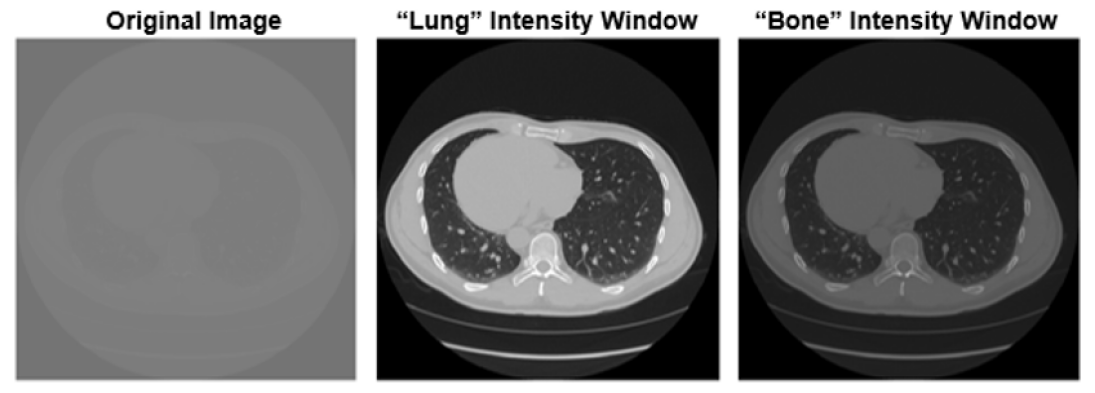

Computed tomography (CT) scan is a medical imaging technique that uses a combination of X-ray equipment and computer technology to produce cross-sectional images, both horizontally and vertically of the body. Compared to x-ray images, these cross-sectional images provide better detail [4]. CT scan turns two-dimensional X-ray images into three-dimensional ones to obtain more information. Specialists examine the images after getting them to determine the patient’s condition. Radiologists can more quickly identify conditions like cancer, cardiovascular disease, infectious disease, trauma, and musculoskeletal diseases by using CT scans. In 1979, South African-American physicist Allan MacLeod Cormack and British electrical engineer Godfrey Hounsfield were awarded Nobel Prize in Physiology or Medicine for the development of computer tomography (CT) [5]. Figure 2 shows a modern CT scanner.

Image enhancement includes making adjustments to digital images to make them more acceptable for display or additional image analysis. Image enhancement enhances the visual quality of the image, supports the clinician’s selection, and ultimately protects the lives of the patients. There are some useful examples and methods of image enhancement: 1. Morphological operations, 2. Linear contrast adjustment, 3. Histogram equalization, 4. Contrast-limited adaptive histogram equalization (CLAHE) 5. Wiener filter, 6. Median filtering and 7. Decorrelation stretch. Medical image segmentation is the procedure used to separate regions of interest (ROIs) from image data, such as that from CT or MRI scans. Identifying the anatomical regions required for particular research is the main goal of segmenting this data. One of the key benefits of medical image segmentation is that separating just essential regions allows for more precise anatomical data interpretation. Segmentation also has the advantage of removing any irrelevant information from a scan, such as air and enabling the separation of various tissues, such as bone and soft tissues. Edge-based, region-based, thresholding approaches and other types of medical image segmentation methods are available. Figures 5, 6, LABEL:fig:image_segmentation represent some image processing techniques.